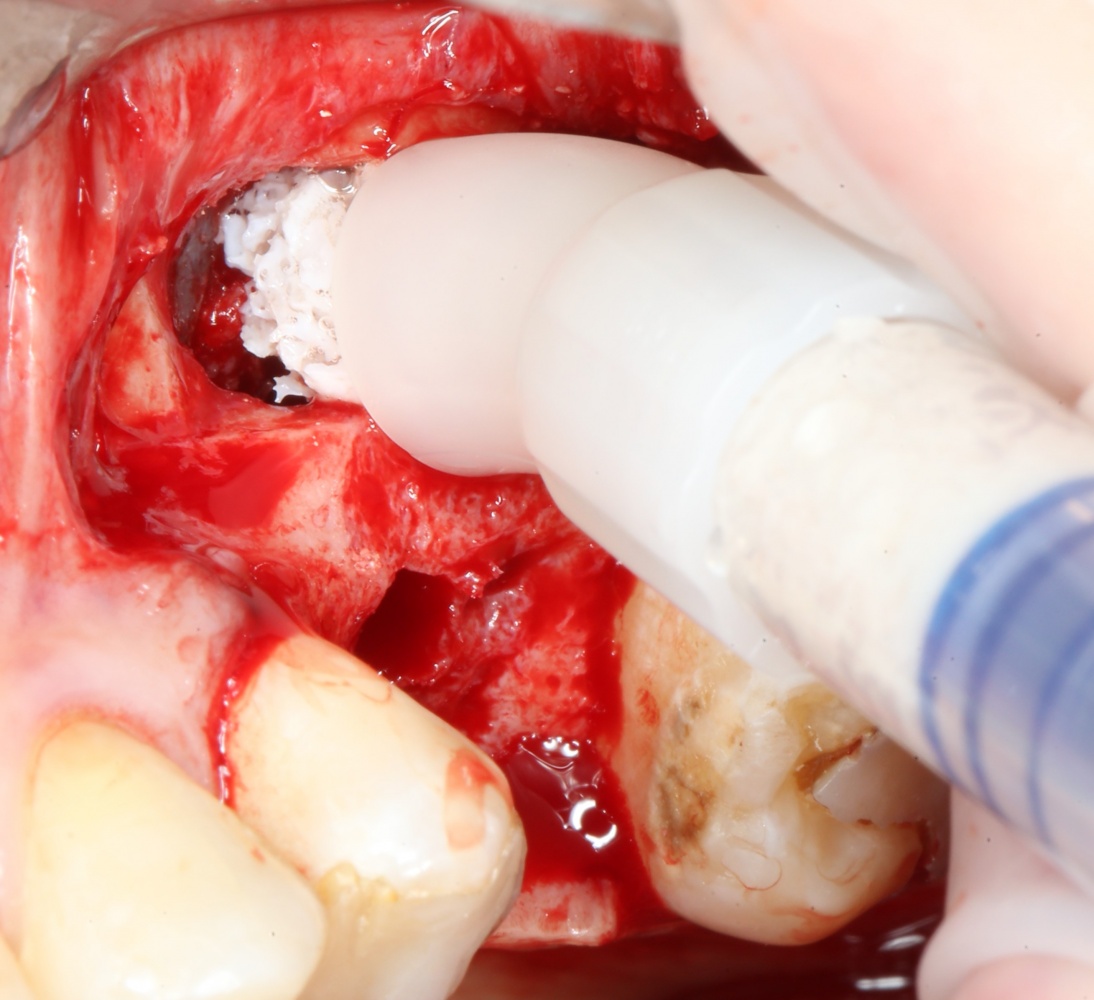

Пришло время вернуться к синуслифтингу и заполнить сформированное ранее субантральное пространство графтом (Geistlich Bio-Oss Pen):

запечатываем заполненное субантральное пространство: